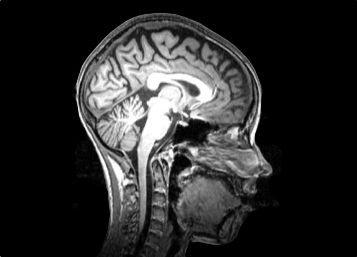

Marie wurde gleich für eine stationäre Therapie zu Stefan Ehrlich geschickt. „Hier hat man mich in eine Röhre gelegt, um Bilder von meinem Kopf aufnehmen zu können. Aber ich habe lieber nicht nachgefragt, was dabei herausgekommen ist“, sagt die Siebtklässlerin. „Ich war so schon völlig fertig.“ Maries Magnetresonanztomographie (MRT) wurde Ehrlich zufolge aber nicht durchgeführt, um zu schauen, ob ihr Hirn geschrumpft war. „Das MRT war zu Forschungszwecken. Ein klinisches MRT ist nur nötig, wenn organische Ursachen wie ein Hirntumor ausgeschlossen werden sollen. Die kognitiven Einbußen kommen manchmal auch ohne eine deutliche Atrophie vor.“

Magnetresonanztomographie

Magnetresonanztomographie/-/magnetic resonance imaging

Ein bildgebendes Verfahren, das Mediziner zur Diagnose von Fehlbildungen in unterschiedlichen Geweben oder Organen des Körpers einsetzen. Die Methode wird umgangssprachlich auch Kernspin genannt. Sie beruht darauf, dass die Kerne mancher Atome einen Eigendrehimpuls besitzen, der im Magnetfeld seine Richtung ändern kann. Diese Eigenschaft trifft unter anderem auf Wasserstoff zu. Deshalb können Gewebe, die viel Wasser enthalten, besonders gut dargestellt werden. Abkürzung: MRT.